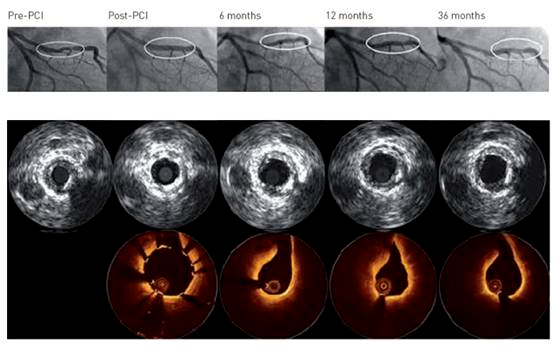

本研究旨在通过高精度的影像学手段——光学相干断层扫描(OCT)与血管内超声(IVUS),在经皮冠状动脉介入治疗(PCI)后的6个月及12个月时间点上,系统性地评估血管愈合的多个关键参数。

具体而言,研究聚焦于支架的体内降解过程及其对血管结构的影响,重点关注支架的可见性变化、血管壁与支架覆盖区域的相互作用,以及新生内膜(即血管内壁为修复损伤而新生的组织层)的生长模式与动态变化。

在12个月的OCT复查中,令人鼓舞的是,超过99%的镁支架已完全降解至肉眼不可见,且未观察到支架网梁贴壁不良的情况,这表明DREAMS 3G支架在体内的生物相容性和降解性能优异,有效避免了传统永久性支架可能带来的长期异物反应。

尽管血管总面积在观察期间未发生显著变化,但值得注意的是,从PCI术后至6个月时,最小管腔面积(MLA)出现了显著的生理性缩小(从6.88 mm²减少至4.75 mm²,p<0.0001),这反映了血管在愈合过程中的自然重构现象。然而,至12个月时,MLA未再进一步显著减小,提示血管结构已趋于稳定,未发生不良的重塑。

研究还揭示了可吸收镁支架植入后新生内膜生长的独特模式。在12个月时,高达89.3%的患者中观察到了明显的新生内膜突出,这是血管愈合过程的一个重要标志。

然而,从6个月到12个月,新生内膜的平均面积却减少了47.4%,这可能反映了新生内膜在成熟过程中的重塑与优化,即从初期的过度增生逐渐转变为更为稳定、功能性的内膜结构。